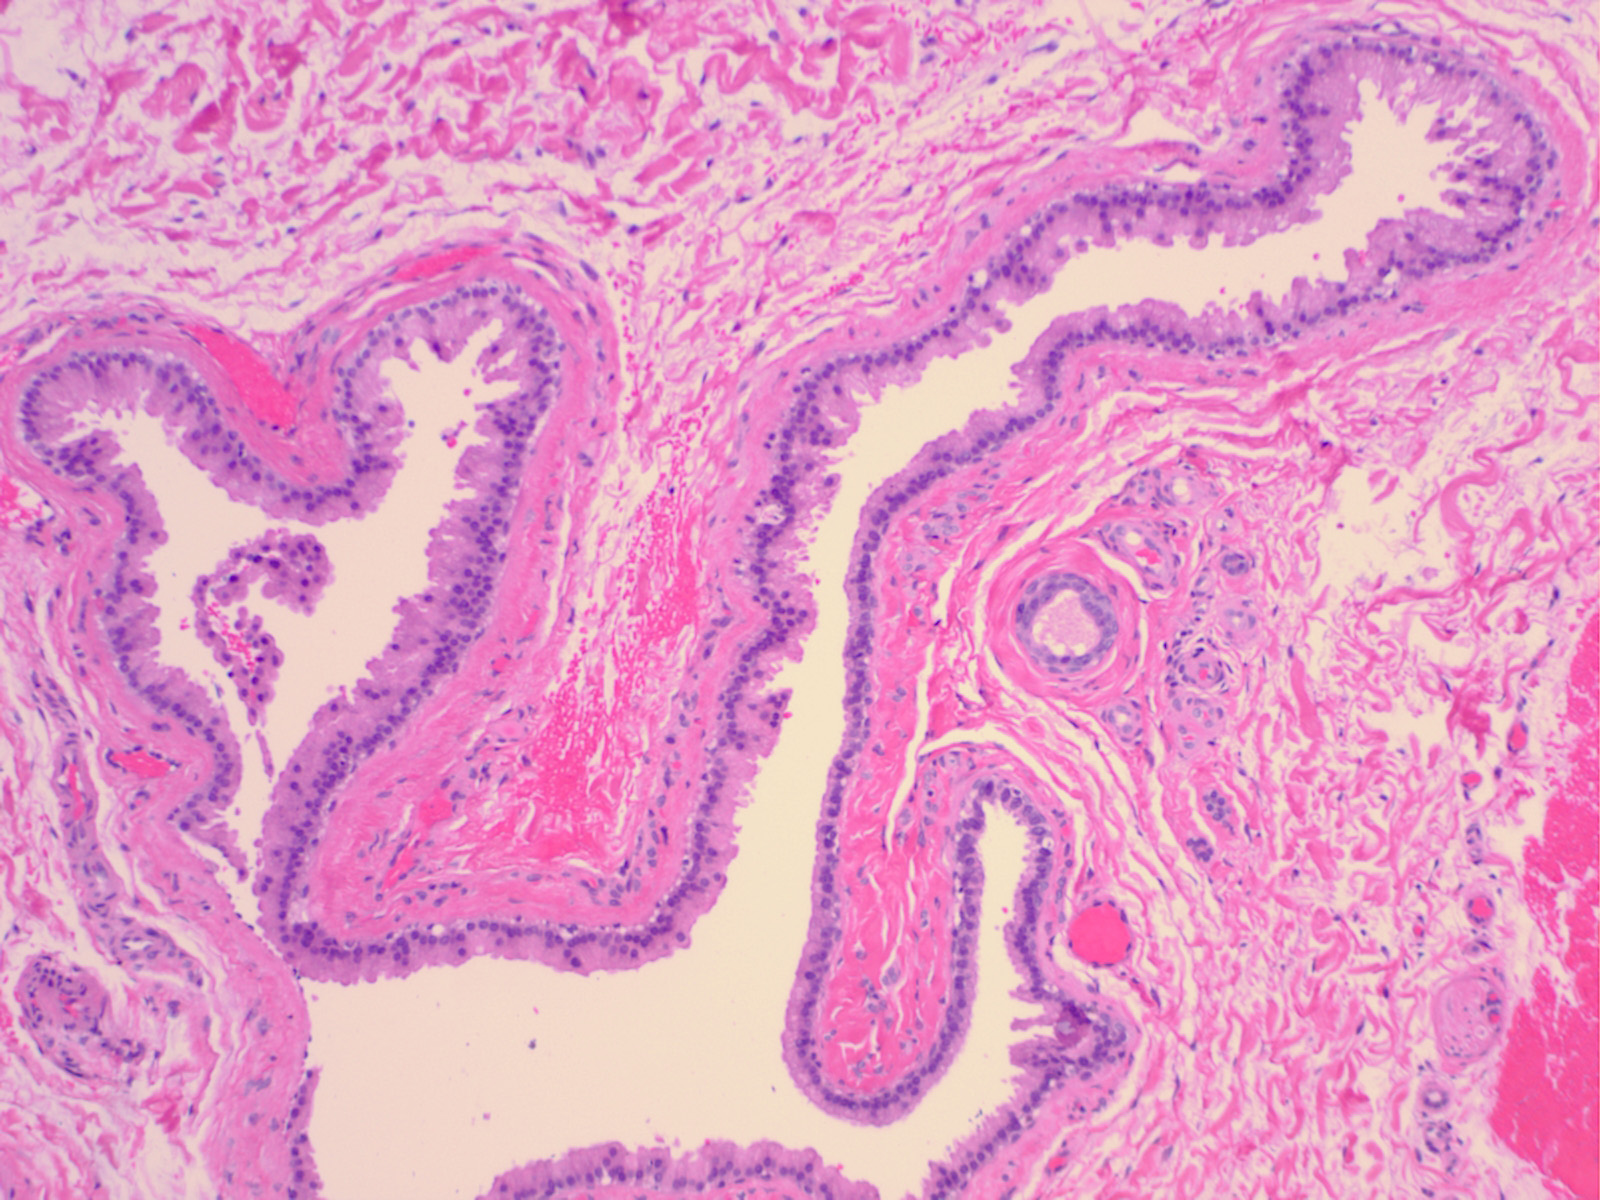

The clinical appearance of a pea-sized cyst near the inner canthus of the eye, which contains a thin clear or pigmented fluid, suggests an apocrine hidrocystoma; however, histologic examination often is required to establish a specific and definitive diagnosis. Upon histologic examination, apocrine hidrocystomas show large unilocular or multilocular cystic spaces within the dermis (see the image below). Apocrine hidrocystomas are more likely to be multilocular than the closely related eccrine hidrocystoma

The cyst wall is lined by apocrine-type secretory epithelium. The innermost layer of the wall is composed of a single (occasionally double) layer of cuboidal-to columnar-shaped cells. The nuclei of these cells are positioned basally. The outer layer of cells composing the cyst wall is formed by myoepithelial cells in which the long axes run parallel to the cyst wall.

Well-organized fibrous tissue surrounds the cyst. Papillary projections extend from the secretory layer into the cyst cavity, depicting decapitation secretion. The secretory cells contain periodic acid-Schiff–positive, diastase-resistant granules and occasionally contain pigment granules, which provide the brown color of the cystic fluid. This pigment is neither melanin nor hemosiderin. On electron microscopy, secretory cells have numerous, dense, lysosomal-type secretory granules typical of apocrine gland cells. They also have an increased number of annulate lamellae, which are unusual in normal apocrine cells.